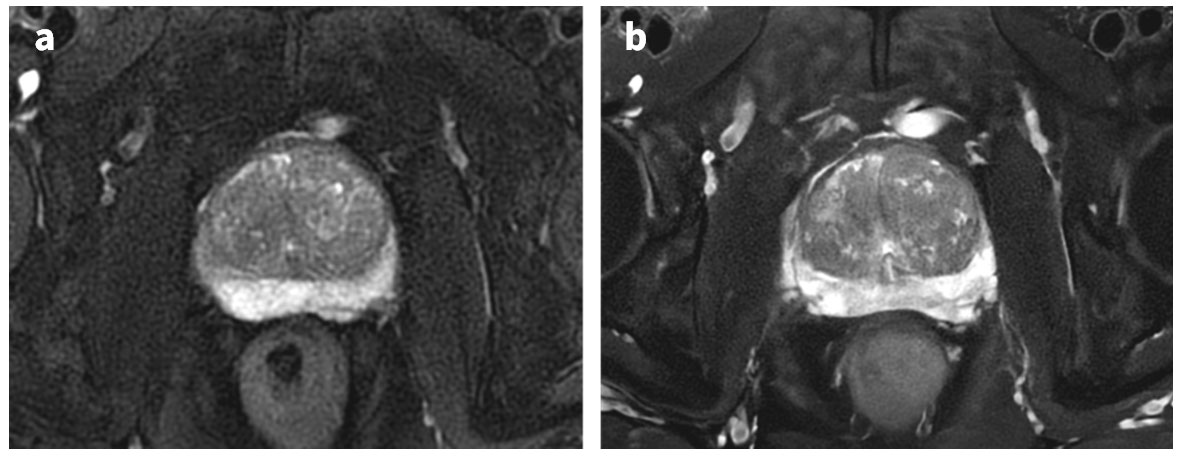

Fig.2aはDiscovery MR 750w 3.0Tで撮像されたDL使用していないT2強調画像, Fig.2bはArtist Evoで撮像されたDLを使用したT2強調画像である. どちらもPROPELLERで撮像された画像であるが, DLを用いた画像(Fig.2b)においては, PROPELLER特有の画像ノイズやストリーク様アーチファクトが一切なく, Cartesian Imageさながらの画質であることがお分かりいただけるだろう. 撮像時間も4:48 (3.0T) →3:12 (1.5T) と, 2/3の時間短縮を図った上で, SNR・分解能・移行域と辺縁域のCNR向上に加えて, 移行域を取り巻く被膜の視認性も大幅に向上している.

Artist_Yokohamaminamikyousai03.jpg

Fig.2 前立腺 T2 PROPRLLER における 3.0T w/o DL と 1.5T w/DLの比較

(a) 3.0T Discovery 750w, without DL, slice厚 3mm, Pixel Size 0.68*0.68

(b) 1.5T, Artist Evo, w/DL, slice厚 3mm, Pixel Size 0.57*0.57